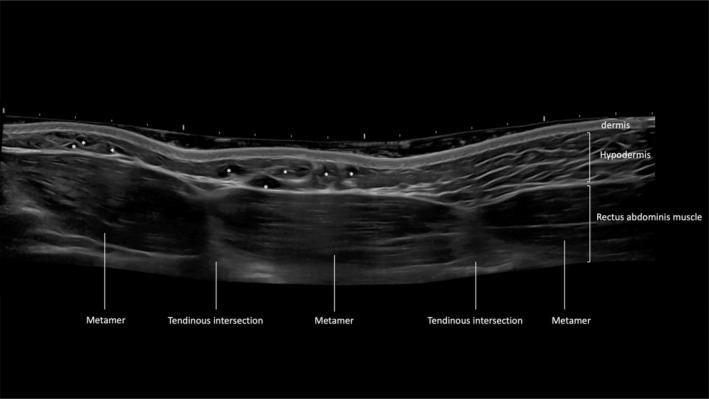

The high-definition abdomen through HA technique (HHD) was implemented on young men with BMI < 24.9, excluding those with obesity or excessive skin laxity. HA gel with large particle sizes (800-1800 μm) and high G prime was chosen based on subcutaneous thickness. Injections were guided by ultrasound into the lamellar fat layer between Camper's fascia and Scarpa's fascia, targeting abdominal metameres for enhancement. Participants completed the Global Aesthetic Improvement Scale.

对体重指数(BMI)<24.9的年轻男性实施通过HA技术实现的高清腹部塑形(HHD),排除肥胖或皮肤过度松弛的患者。根据皮下厚度选择大粒径(800 - 1800μm)和高G'值的HA凝胶。在超声引导下将其注入坎珀筋膜和斯卡帕筋膜之间的板层脂肪层,针对腹部节段进行强化。参与者完成全球美学改善量表评估。